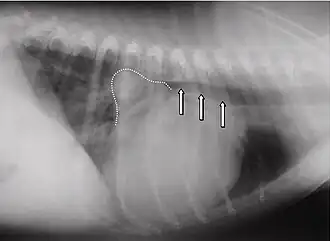

Die häufigsten Anzeichen einer verschlechterten Herzfähigkeit sind: abnehmende Leistungsfähigkeit, Husten, nächtliche Unruhe und Dyspnoe. In der Auskultation sind in den meisten Fällen holosystolische Herzgeräusche konstanter Intensität in verschiedensten Lautstärken (Grad 1 bis Grad 6) wahrnehmbar. Das lauteste Geräusch (Punctum maximum) der Mitralklappe liegt beim Hund im 5. Interkostalraum auf Höhe der Herzspitze. Im Röntgenbild ist häufig ein vergrößertes Herz feststellbar. Der linke Vorhof kann hierbei in Form eines Dreieckes („Mitralisdreieck“) nach kaudo-dorsal hervortreten. Die häufig feststellbare Abwinkelung zwischen Luftröhre und Wirbelsäule kann einem parallelen Verlauf gewichen sein, teilweise kann der Vorhof sogar die Luftröhre komprimieren und infolge der hierdurch verursachten mechanischen Reizung die Hustensymptome noch verstärken. In fortgeschrittenen Fällen liegt ein Lungenödem vor. Das Elektrokardiogramm ist häufig wenig spezifisch, teils sind Hinweise auf einen vergrößerten Vorhof (verlängerte P-Welle, über 0,04 Sekunden) oder eine vergrößerte Hauptkammer (QRS-Komplex länger als 0,06 Sekunden) erkennbar. Daneben kann es zur Ausbildung von Vorhof- oder Kammerextrasystolen kommen, in einigen Fällen wird ein Vorhofflimmern beobachtet. Dieses Symptom ist bei Hunden mit funktionellen Mitralinsuffizienzen aufgrund einer dilatativen Kardiomyopathie häufig. Echokardiografisch ist eine Mitralklappeninsuffizienz anhand einer Doppleruntersuchung leicht erkennbar. Daneben treten als Effekte auf: erweiterte Hauptkammer aufgrund der Volumenüberlastung, häufig Hyperkontraktilität aufgrund von Kompensationsmechanismen, deutlich vergrößerter Vorhof.